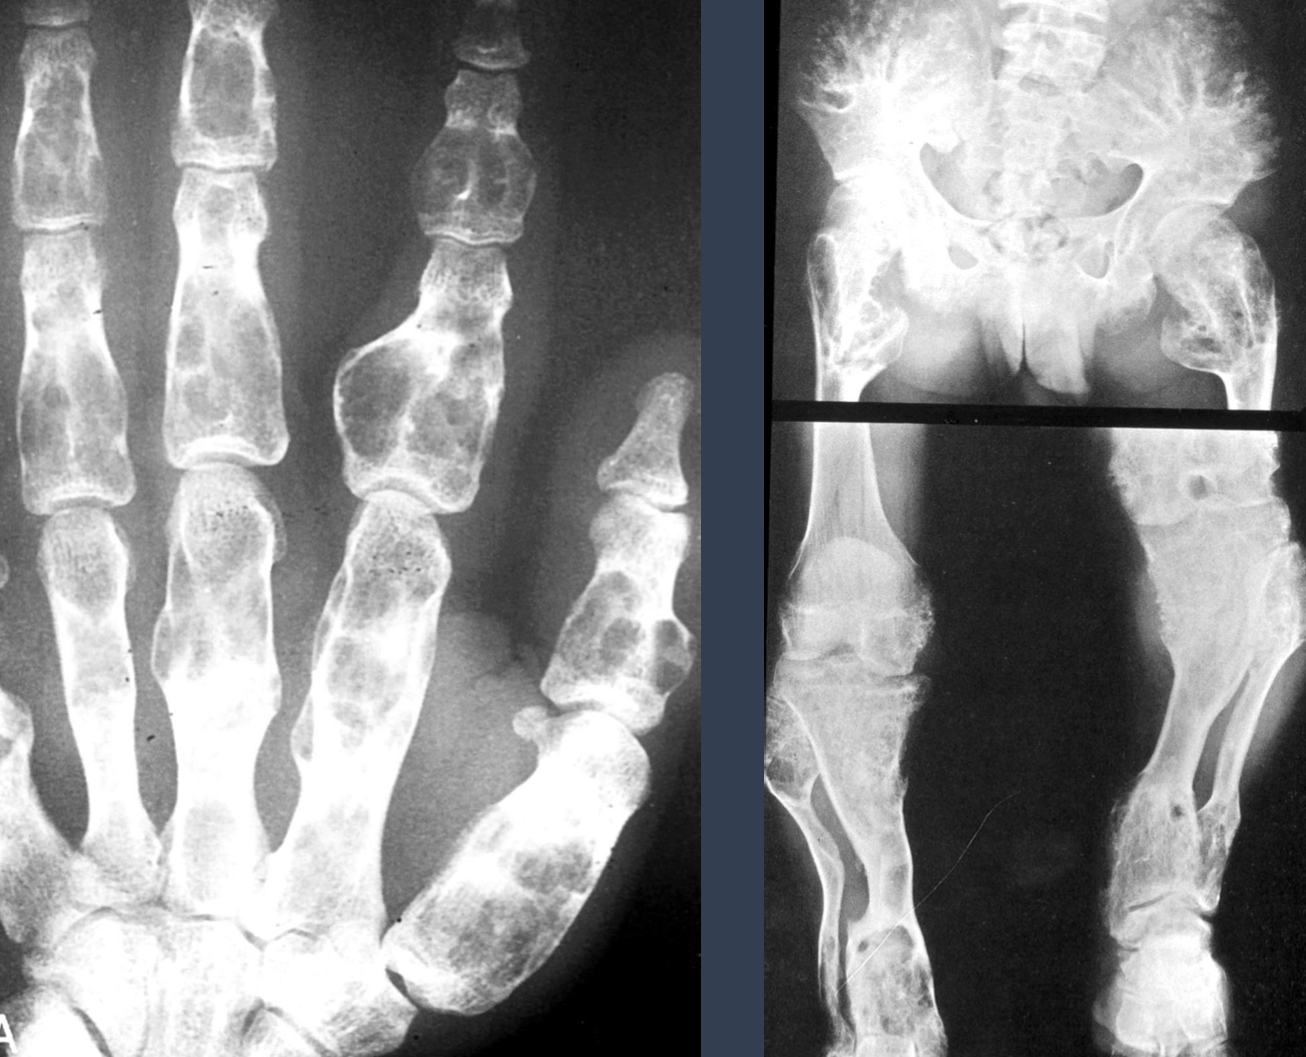

what is this?

acral mets

what is the triad associated with it?

Gardner Syndrome

well efined

opaque

clean borders

multiple myeloma